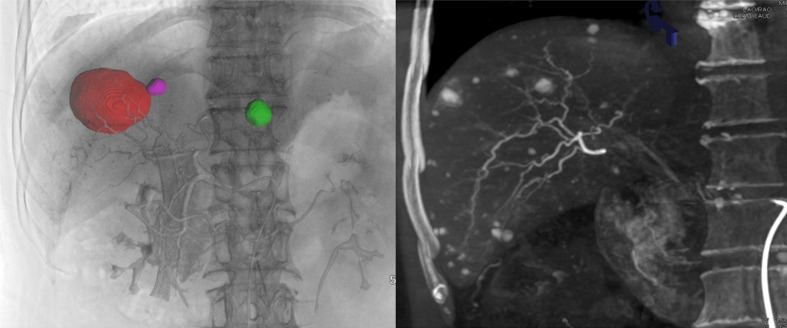

尽管锥形束计算机断层扫描(CBCT)在肝脏恶性肿瘤的介入治疗中发挥着至关重要的作用,但由于操作不规范、介入放射医师对 CBCT 的认可度有限等复杂因素,CBCT 尚未完全融入临床实践。为此,中国介入医师学会发布了一份共识声明,旨在规范和推广 CBCT 在肝脏恶性肿瘤介入治疗中的应用。该声明总结了 CBCT 扫描技术和操作标准,并强调了其在临床实践中的潜在应用。

Despite its crucial role in interventional therapies for liver malignancy, cone-beam computed tomography (CBCT) has not yet been fully integrated into clinical practice due to several complicating factors, including nonstandardized operations and limited recognition of CBCT among interventional radiologists. In response, the Chinese College of Interventionalists has released a consensus statement aimed at standardizing and promoting the application of CBCT in the interventional therapies for liver malignancy. This statement summarizes CBCT scanning techniques, and operational standards, and highlights its potential applications in clinical practice.